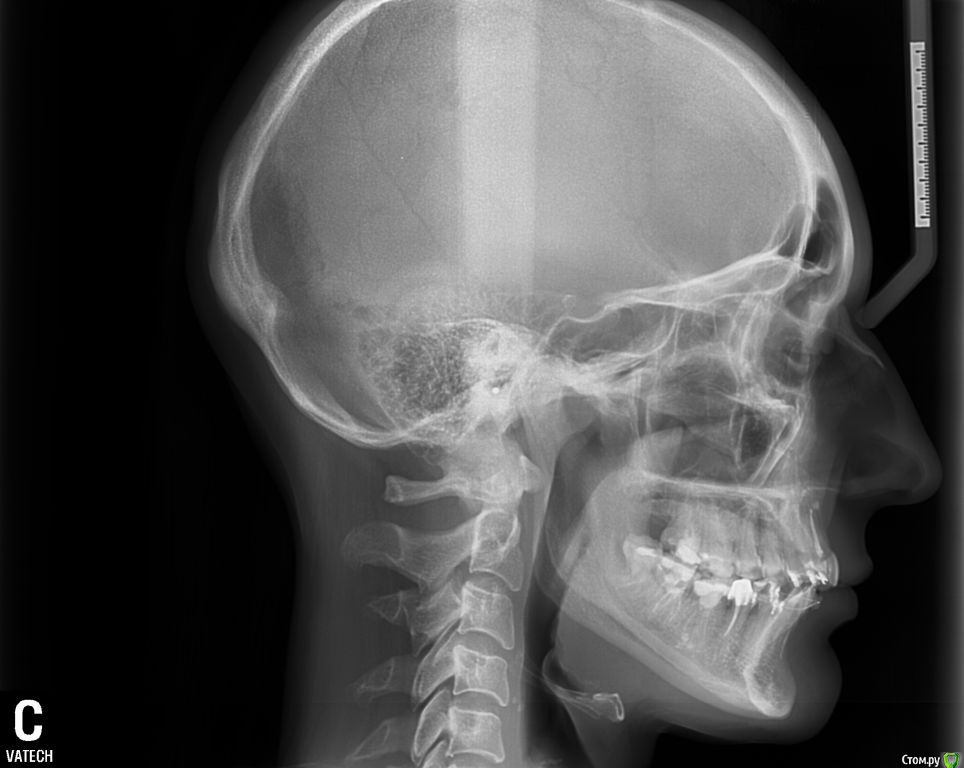

ol"ga Опубликовано 15 августа, 2015 Поделиться Опубликовано 15 августа, 2015 (изменено) Здравствуйте, Уважаемые Доктора!Очень нуждаюсь в вашей помощи. Мне 35 лет, в октябре прошлого года была установлена частичная брекет-система : на верхней ( 6 зубах, от клыка до клыка) лингвальная брекет-система и нижней ( 9 зубах) вестибулярная брекет-система и были изготовлены окклюзионные накладки на боковых зубах нижней челюсти. Перед ортодонтическим лечением никаких снимков не делала. За первый месяц ношения лингвальных брекетов верхняя челюсть достаточно быстро выдвинулась вперед, результат меня устраивал, но в дальнейшие 5 месяцев челюсть все продолжала выдвигаться вперед, в результате в прикусе впереди образовалась щель между челюстями в 5-7 мм, нижняя челюсть не так быстро успевала выдвигаться вперед, заметила что я неосознанно выдвигаю нижнюю челюсть пытаясь подстроиться под верхнюю, но речь была свистящая, шипящая, жевала на правую сторону, т.к. на левую было неудобно (по ощущениям, слева окклюзионная накладка была ниже, чем справа). Так проходила 6 мес., результат меня не устраивал, верхние зубки оставались кривыми, стали выпирать клыки, врач сказал, что это от давления дуги, а верхняя челюсть сильно выдвинулась вперед и стала похожа на открытый прикус. Мой врач сказал, что положения кривых наклонов зубов лингвальные брекеты не исправляют, а выставляют зубки в ряд, и предложил бесплатно поменять на вестибулярную брекет-систему. В конце апреля сделали панорамный снимок, трг в боковой проекции и переустановили брекет-систему на все зубки верхней челюсти, и на нижней кроме 7-к и 8-к, убрали окклюзионные накладки, но челюсть у меня не сомкнулась в привычном положении, заметила, что зубки на нижних шестерках, где были накладки, как бы просели в десну. Врач сказал, что это временно, все выровняется. Первую неделю зубки болели обычно как после активации аппарата, затем появилась боль в районе правого сустава, сначала после приема пищи, жевать я продолжала на правую сторону, пыталась приловчиться, куда удобнее, а затем боли продолжались и в покое, несколько раз просыпалась ночью от боли, пила нимесил. В этом остром периоде заметила асимметрию лица, по ощущениям нижняя челюсть «съехала» вправо, сомкнуть челюсть в таком положение не могла, сильная боль была, я ее сдвигала влево, получался перекрестный прикус (это было спустя 3 недели после установки брекет-системы). Обратилась к своему ортодонту, он сказал, что челюсть перестраивается под правильное положение зубов, могут быть боли, а асимметрию он не видит. Боли продолжались. Челюсть я так и не могла сомкнуть в « правильном» положении. Обратилась в другую клинику к ортодонту, поставили дисфункцию ВНЧС, 2 раза делала миорелаксацию с интервалом месяц (в конце мая и июня), рекомендовали не нагружать сустав и широко не открывать рот, все это я соблюдала, ела только только на левую сторону (до сих пор на нее и жую), острая боль постепенно сменилась просто дискомфортом в области правого сустава. После первой процедуры миорелаксации на второй день я смогла без боли сомкнуть челюсть в « правильном» положении, но комфортнее было ее держать в расслабленном состоянии, чуть левее, в основном я так и ходила. В это время я заметила, что у меня верхняя челюсть сместилась вправо, верхний левый зубной ряд начал мешать языку в его привычном положении, все зубки на обеих челюстях как бы наклонились в сторону языка, создалось впечатление, что челюсть сузилась. Еще постоянно царапал край дуги на верхней правой 7-е, мне ее 2 раза подпиливали и убирали щипцами, но через несколько дней опять край вылазил и накалывал щеку, решили вообще убрать замок с правой 7-и т.к. на щеке постояна была незаживающая язва от этой травмы. На днях соскочила дуга с левой верхней 7-и. Но врач сказал, что это невозможно, что воспалительный процесс в суставе он снял и я могу обратиться к своему ортодонту для продолжения ортодонтического лечения. Я обращалась еще к 5 специалистам специалистам. Никто проблемы не видит. один из специалистов в результате обследовал сделал оттиски зубов и дал заключение: Диагноз : Миофасциальный болевой синдром лица с дисфункцией височно-нижнечелюстного сустава. Дислокация диска с вправлением в левом ВНЧС.(вентральная). Бруксизм. Другой предложил шину на нижнюю челюсть, но только после снятия брекетов с нижней челюсти.Продолжаю поиски. Сделала трг в прямой, боковой и подбородочно- теменной проекции, кт обеих суставов, ищу специалистов которые могут мне помочь в моей проблеме, но в моем городе это проблема. Бруксизма за собой не замечала, родные тоже, зубами не скреплю, во сне не жую, но 100% утверждать не могу. Проблем с ВНЧС никогда не было, ни щелчков, ни хруста, ничего. На данный момент иногда поднывает в области правого сустава, а в основном чувство дискомфорта в нем. Уважаемые Доктора, подскажите, пожалуйста, как в моем случае должен проходить план лечения, можно ли исправить асимметрию лица, можно ли вернуть верхнюю челюсть на место и почему врачи не видят этой проблемы, очень нуждаюсь в вашей помощи, хочется вернуть свое лицо и функциональность внчс. Эпикриз.doc Изменено 15 августа, 2015 пользователем ol"ga Ссылка на комментарий

Skip Опубликовано 23 августа, 2015 Поделиться Опубликовано 23 августа, 2015 Вопрос по ТРГ в боковой проекции. Эти два исследования в какой промежуток времени проводились? Ссылка на комментарий

ol"ga Опубликовано 23 августа, 2015 Автор Поделиться Опубликовано 23 августа, 2015 Ровно 4 мес., там каждое фото с датой внизу, первое трг еще с лингвальными брекетами, его сделали перед переустановкой на вестибулярную брекет-систему Ссылка на комментарий